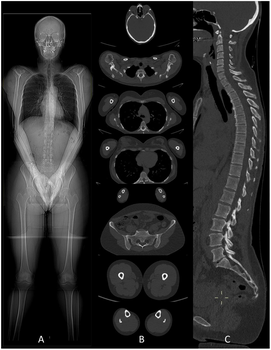

L’imagerie médicale regroupe des examens qui permettent d’obtenir des images de l’intérieur du corps. Ces images aident les professionnels de santé à poser un diagnostic, à suivre une maladie ou à évaluer un traitement.

Disposant de toutes les modalités d'examen (Imagerie par Résonnance Magnétique (IRM), scanner, artériographie diagnostique et interventionnelle, échographie, mammographie, radiologie générale) et fort d'une équipe de 30 radiologues et 4 médecins spécialistes en formation, le Service d'Imagerie médicale de la Citadelle exerce son activité sur 4 sites (Citadelle, Herstal, Laveu et Valdor).